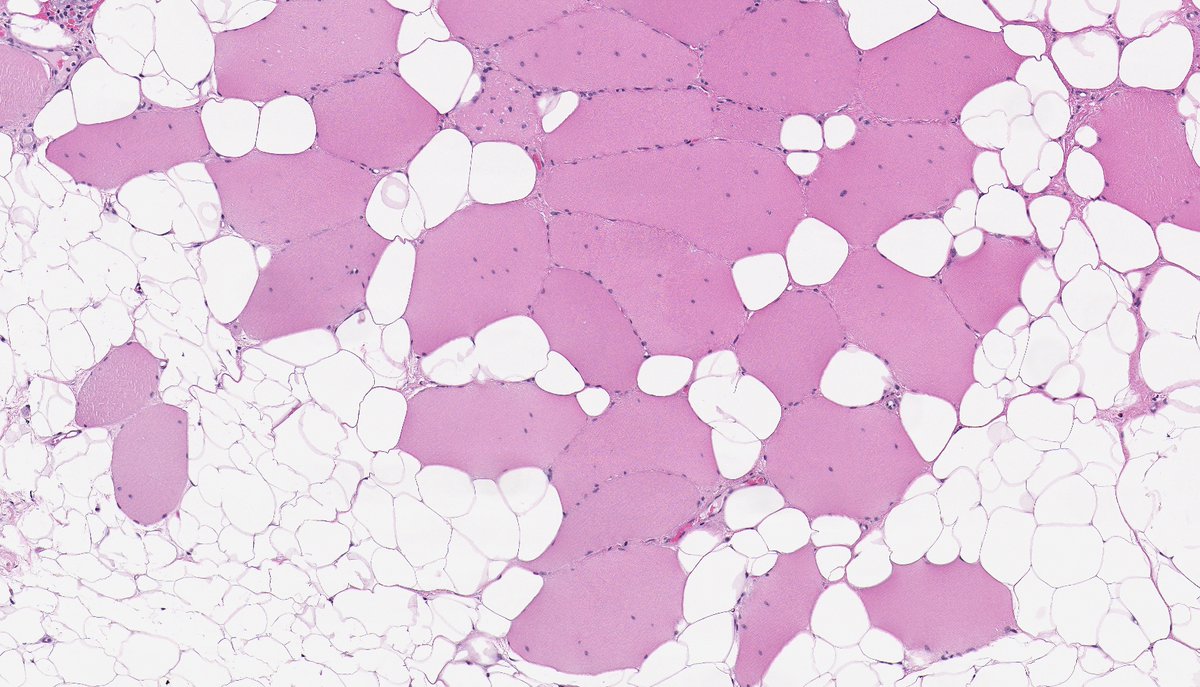

Anatomical Pathologist - UBC #BSTpath #GYNpath